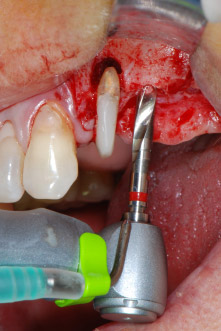

En primer lugar, en un intento por gestionar el problema endo-periodontal, el resto de la superficie radicular se desbridó con cuidado con un equipo piezoeléctrico (Piezomed de W&H, utilizado con el inserto S1 con forma de espátula, concebido en un principio para la erosión de la pared lateral del seno) (figura 4). A continuación, el ápice se erosionó con el mismo instrumento para eliminar el tejido apical infectado residual y reducir las posibles ramificaciones accesorias del canal radicular (apicectomía) (figura 5). No fue necesario realizar un retrorellleno, puesto que la obturación ortógrada se acababa de revisar.

En el siguiente paso, los lechos del implante se prepararon en las posiciones 25 y 26 con instrumentos rotatorios, utilizando un contra-ángulo con un coeficiente de transmisión de 20:1 (WS-75 L, W&H), junto con el nuevo potente motor de implantes Implantmed de W&H (figuras 8 y 19).